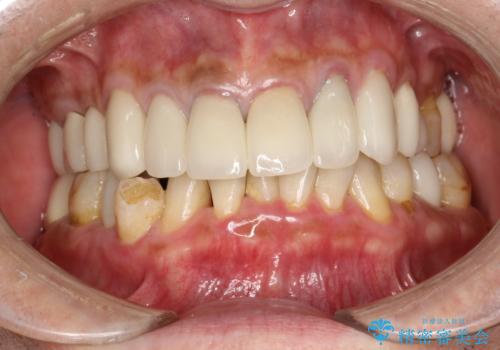

- 約1年ぶりの来院のため、着色や歯石がかなりついてしまっため、綺麗にしてほしいとのことでした。PMTC30分コースを行いました。

PMTC(保険外治療)は、毎日の歯磨きで落としきれない汚れや、コーヒ、紅茶などによる着色・タバコのヤニなどの着色も除去します。目には見えない歯と歯の間・歯肉の境目などに残っているプラーク(歯垢)もしっかり取り除きます。PMTCでは専門的な機械や材料を使用して、徹底的に汚れを除去するため、虫歯・歯周病・口臭予防などにつながります。